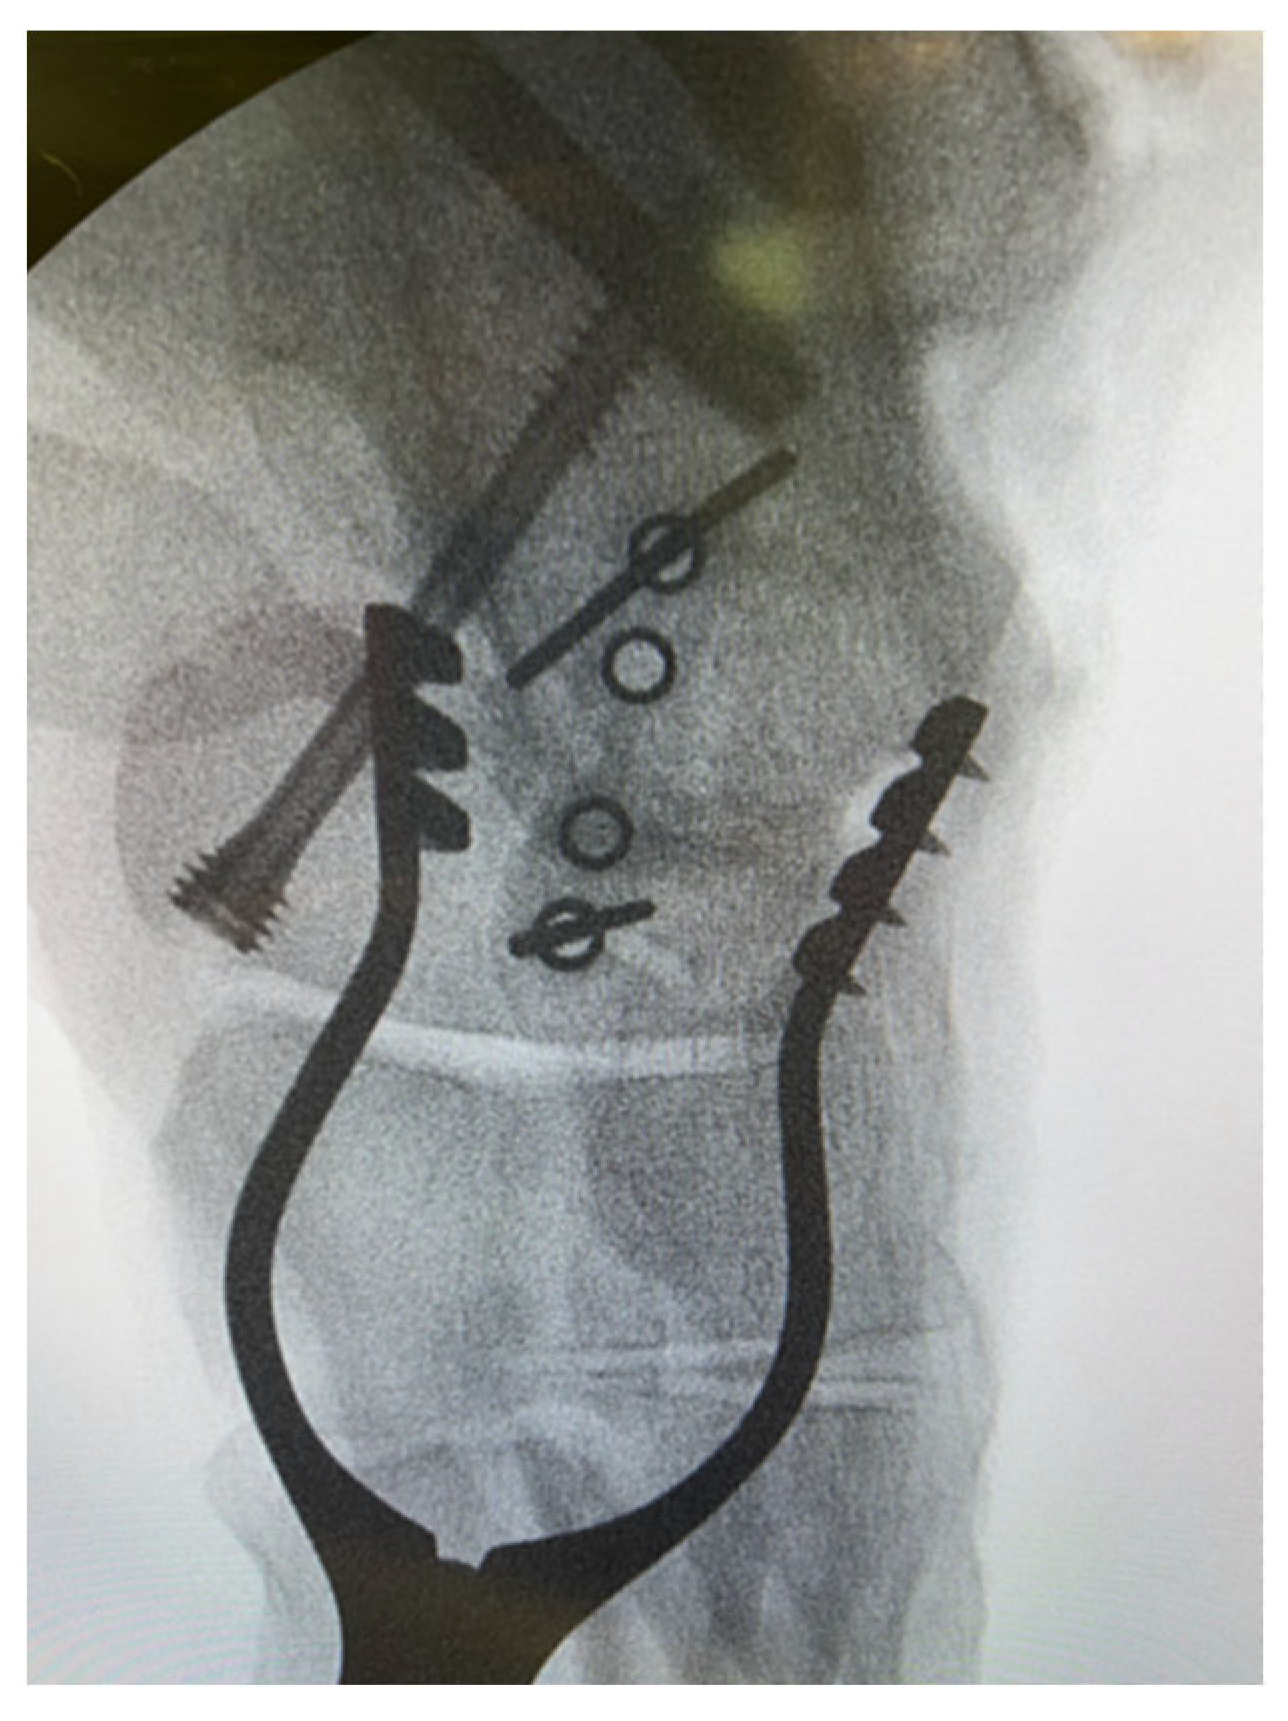

We highlight that the ‘perfect circle technique’ was implemented prior to introducing the implants to avoid undesirable joint penetration, which would inevitably compromise the compression across the fusion site and result in pain and patient dissatisfaction. This ‘perfect circle technique’ involved the use of the staple guide along with the corresponding staple guidewires. This construct was then screened with the image intensifier, and the radiograph was considered satisfactory when the holes on either side of the staple guide were perfectly superimposed (Figure 1).

This translates to an image of a round circle in the guide rather than an ellipse. To quickly achieve perfect circles without specific instrumentation, the surgeon should manipulate the position of the foot in relation to the drill guide, which remains in place throughout the wire and subsequent pin placement. Moreover, a true lateral view is highly recommended for the surgeon to confirm that the position of the wires is not intra-articular. To effectively prevent this complication from happening, the surgeon should be mindful of the orientation of the joints (e.g., saddle-shaped calcaneocuboid joint).

Figure 1. Intra-operative image of talonavicular joint fusion demonstrating the ‘perfect circle technique’.